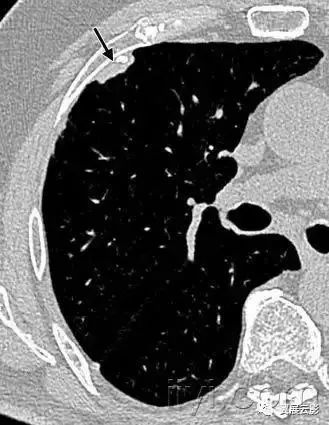

六、顶冠或肺尖帽

病理:是肺尖的帽状病变,常由肺内或者胸膜的纤维化,向下牵拉胸膜外脂肪,也可能是慢性缺血导致脏层胸膜的透明斑形成所致。随年龄增长,发病率增加。主动脉撕裂导致的血肿,或者炎症或者肿瘤,导致液体积聚在胸膜腔或者壁层胸膜外,也可以出现此征象。

平片和CT:常见表现是均匀的软组织密度,位于单侧或者双侧肺尖之上呈帽状,下界尖锐且不规则。厚度可变,甚至可达30mm。有时候在横断CT上,肺尖帽可以类似肺尖的实变。